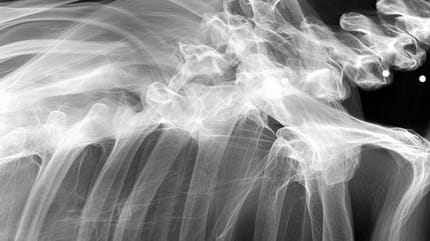

Einige Jahre nach der erfolgreichen Adoption geht Momos Halter mit ihr zum Tierarzt. Die Hündin hat zunehmend Schwierigkeiten, sich zu bewegen. Ein Röntgenbild soll Klarheit bringen und sorgt für eine böse Überraschung. Im Behandlungszimmer wird es plötzlich still.

Der Tierarzt erklärt, dass die Hündin eine sehr schwere und gewalttätige Vergangenheit hatte. Die Aufnahme zeigt, dass sie wahrscheinlich zur Massenzucht missbraucht wurde. Doch das ist nicht alles. Die Hündin leidet auch an Arthritis und Hüftdysplasie und verbirgt ein weiteres Geheimnis.

Der Tierarzt stellt außerdem fest, dass der Körper der Hündin von Kugeln durchsiebt ist. Eine der Kugeln hat nur knapp ihre Wirbelsäule verfehlt. Glücklicherweise beeinträchtigt keine der Kugeln ihr Leben heute ernsthaft. Heute führt die Hündin endlich das Leben, von dem sie immer geträumt hat, wie die Kollegen von Newsweek berichten.